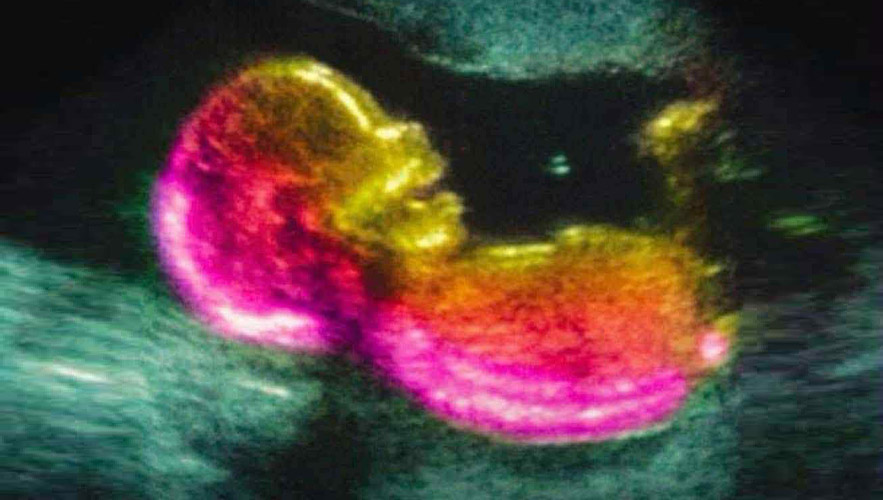

A new study featured in The Journal of Immunology has boosted the momentum behind expanding research on the gut-brain link. Researchers are now more closely investigating how the mother's microbiome could affect the likelihood of neurodevelopmental disorders, such as autism.

Although genetics are a major factor in autism, researchers are also exploring environmental and biological factors that occur during pregnancy. This new study points to one potential route: immune signals influenced by gut bacteria.